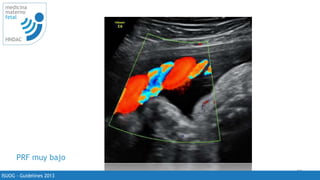

PRF muy bajo